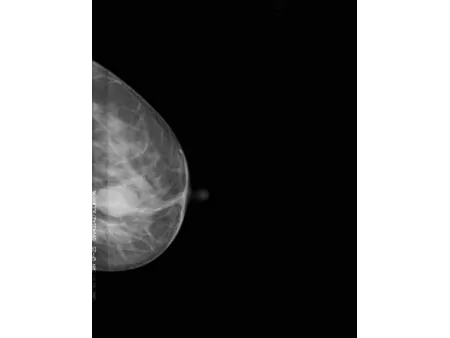

El detector plano CMOS, reconocido por su alta sensibilidad, permite obtener imágenes mamarias con gran nivel de definición. Este mamógrafo también incluye el software especializado Console, que utiliza algoritmos avanzados de posprocesamiento para mamografía, facilitando la visualización de estructuras finas y mejorando la precisión en la interpretación clínica. Con una capacidad de resolución de 60 líneas por centímetro, es capaz de detectar microcalcificaciones tan pequeñas como 0.1 mm, lo que refuerza su utilidad en programas de detección precoz de cáncer de mama y en evaluaciones clínicas más específicas.